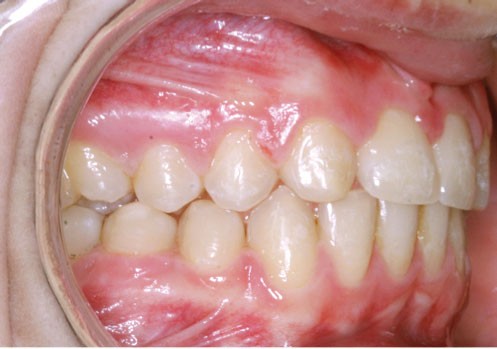

Ludivine T. âgée de 12 ans et demi présente une agénésie des deux incisives latérales maxillaires dans un contexte occlusal de classe II division 2 (fig. 1 à 3).

Les vues endo-buccales (fig. 2) montrent la classe II division 2 occlusale associée à une forte supraclusion incisive et l’évolution spontanée de 13 et 23 pratiquement en place de 12 et 22. Il persiste cependant un diastème disgracieux entre 13 et 11.